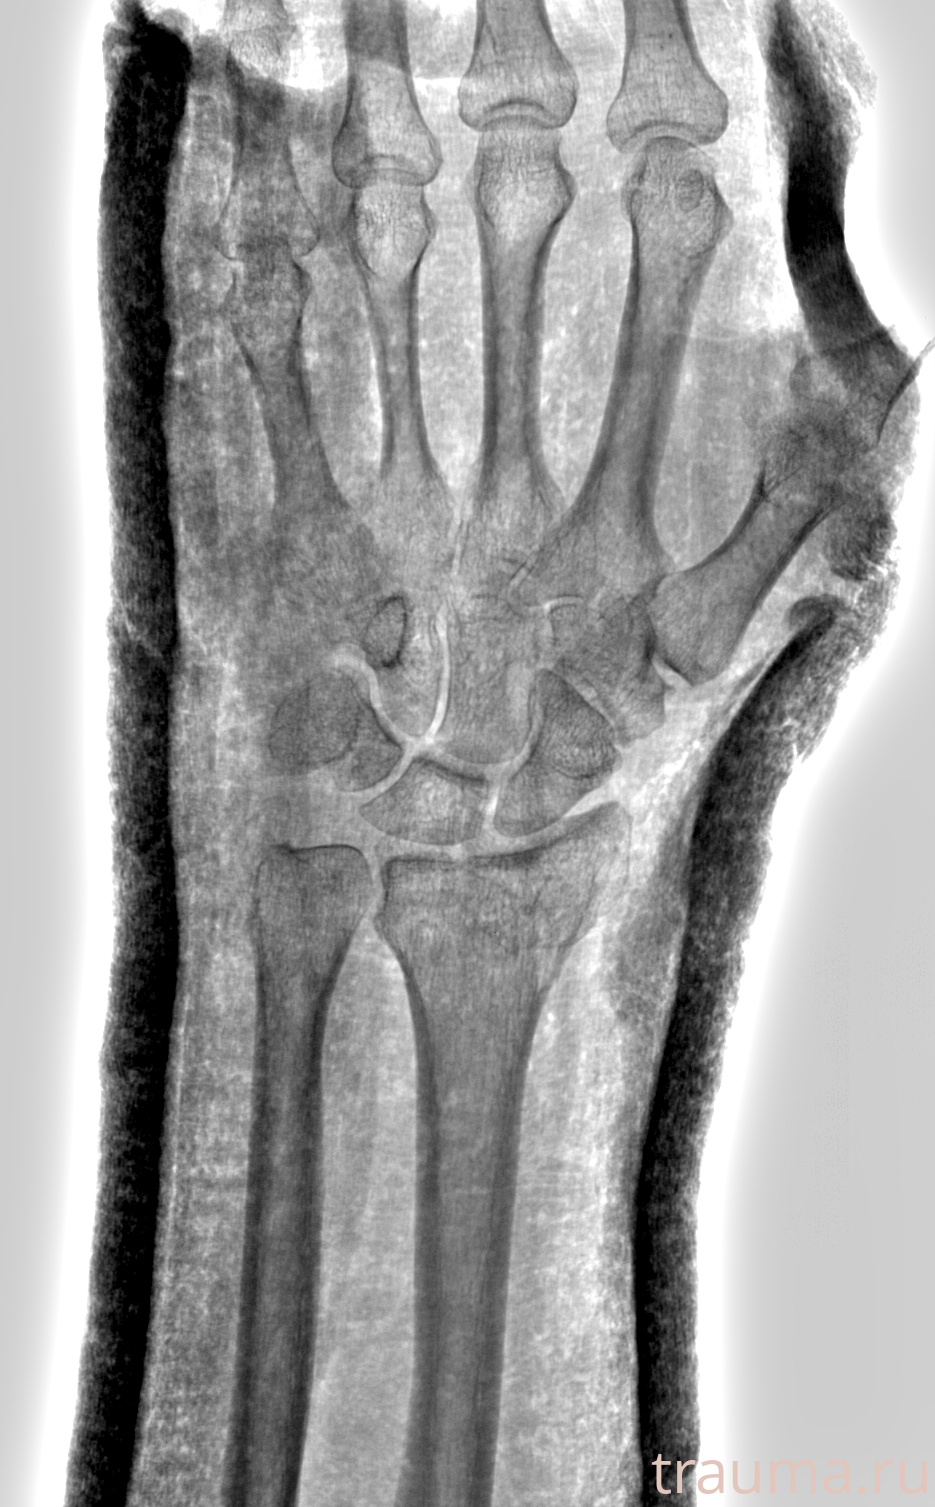

Рентгенограммы

Рентген на дому: по вашему адресу приезжает врач-рентгенолог, травматолог-ортопед с мобильным рентгеновским аппаратом, проводит диагностику травмы или заболевания, делает необходимые рентгенограммы, дает рекомендации по дальнейшему лечению. Получить качественные снимки в домашних условиях возможно благодаря уникальной методике, разработанной МосРентген Центром для института  Склифосовского